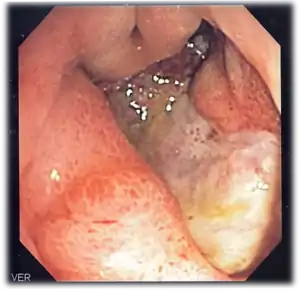

Endoscopic still of duodenum of patient with celiac disease showing scalloping of folds.